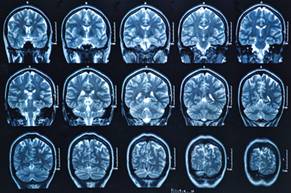

可以看到人体内部的MRI

恩斯特:最有价值的应用是核磁共振成像(MRI),能让你看到人体内部。事实上,MRI对我个人来说也很重要。2007年的一天,我坐在书桌旁,突然感到天旋地转。去医院检查,医生用MRI扫描我的脑部,发现一处血管狭窄,限制了血液流动。这种情况几年前再次出现,我在街上散步时突然觉得左腿疼痛,一会儿功夫就寸步难行了。通过MRI诊断,我患了动脉阻塞。心脏搭桥手术使我恢复了健康。

MRI能让你看到人体内部